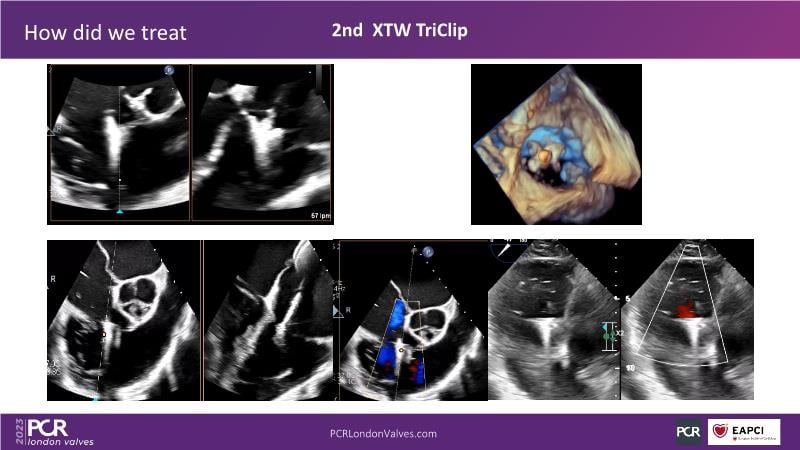

This session offers an opportunity to engage in a real case discussion led by an advanced Heart Team. Participate in discussions on controversial decision-making scenarios and stay informed about the latest clinical evidence related to MitraClip, Tendyne, and TriClip therapies.